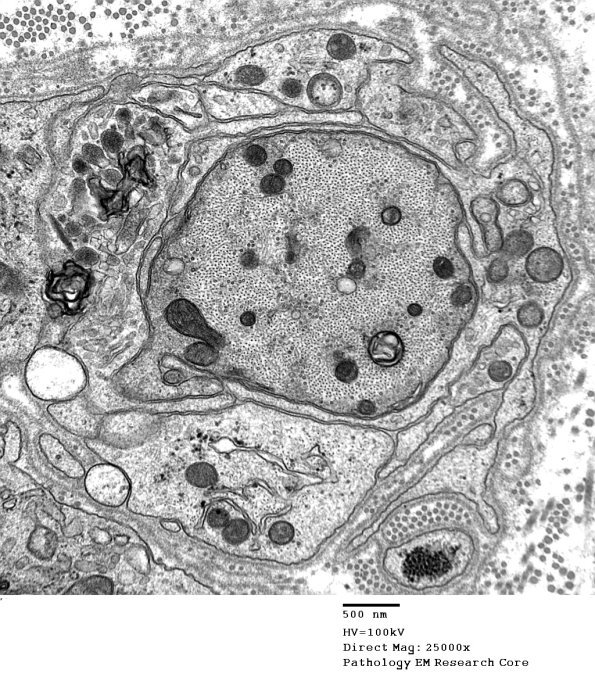

Higher magnification of image #4B8. (electron micrograph)